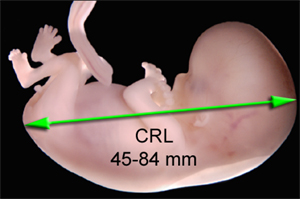

anne karnında bebek fotoları

4 haftalık bebek görüntüsü 25 haftalık bebek 25 görüntüsü

anne karnında 4 haftalık

anne karnında 4 haftalık